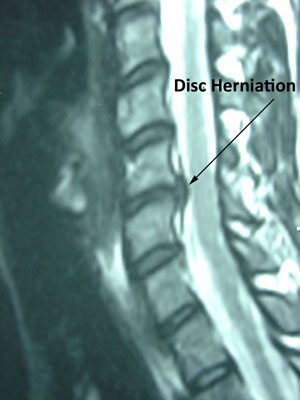

In the same way that an MRI reveals several disc herniations in a patient with minimal to no symptoms, the disappearance of pain in a patient with pain due to a disc herniation may be due to the disc's not reducing at all ... or reducing a little or even getting larger. The goal of treatment at Aurora Chiropractic Center in Juneau is pain relief which entails a reduction of irritating factors be they mechanical, chemical or other.

When pain due to a disc herniation finally goes away, it is often a cause for celebration, but curiosity as to what happened to the disc may come into question. Amazingly, the size of the disc herniation may completely shrink, stay the same, or even enlarge as you heal and become relieved of your spine and/or extremity pain under non-surgical care. Keep in mind that 76% of us show a herniated disc on an MRI even when we have no symptoms. (1)

Regardless the size or size reduction, Juneau disc herniation patients are relieved of their pain even though the disc herniation may not 100% reduce. The reason for the pain relief is the reduced compression and inflammation on the nerve root at the spine level as a result of non-surgical care. That is also why we can have a disc herniation and experience no pain - the pressure on the nerve is below the level that causes pain. Finally, a disc herniation may regress or even disappear in a number of patients. This knowledge of the disc's behavior reduces the significance of radiological findings like MRI in deciding on surgery for a disc herniation. (5) A thorough clinical examination and treatment plan to include careful clinical monitoring of symptoms ensures the best clinical treatment plan and outcome.